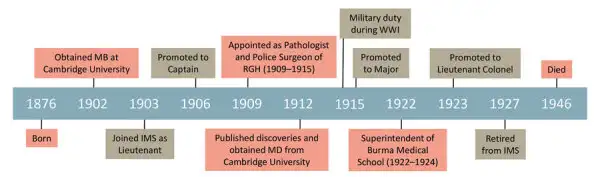

然而,类鼻疽的故事远比越战更为古老。它的历史可以追溯到1911年的缅甸仰光,一位名叫阿尔弗雷德·惠特莫尔的英国病理学家在一个阴雨连绵的午后,解剖了一具令人困惑的尸体。他不会想到,自己即将揭开一种将困扰人类整整一个世纪的致命疾病的面纱。

1911年的仰光正值雨季,空气潮湿而闷热。阿尔弗雷德·惠特莫尔,这位来自英国坎布里亚郡的病理学家,正在仰光综合医院的停尸房里工作。他原本的梦想是在伦敦或孟买这样的大城市施展才华,但命运的安排将他送到了这个远离帝国中心的偏远角落。然而,正是这种远离,让他获得了独立思考和研究的机会。

惠特莫尔意识到自己可能发现了一种全新的疾病。他与印度助手克里希纳斯瓦米一起,开始系统地研究这种神秘的感染。在接下来的几年里,他们记录了超过两百个病例,其中绝大多数是吗啡注射者。惠特莫尔推测,这些瘾君子使用的被污染的注射器和稀释液可能是细菌进入人体的途径。1912年,他在《印度医学公报》上发表了这一发现,将这种疾病首次呈现在世人面前。

这位谦逊的病理学家用自己的名字命名了病原体——“伪马鼻疽杆菌”,意为"类似于马鼻疽的杆菌"。然而,真正以他名字命名的并非细菌本身,而是这种疾病:惠特莫尔病。这个名字至今仍在医学文献中被使用,作为对这位被遗忘的先驱者的纪念。

然而,命运对惠特莫尔并不仁慈。第一次世界大战爆发后,他被召回军队服役,再也没有机会继续他的类鼻疽研究。当他战后回到缅甸时,被分配到行政职位上,远离了他热爱的实验室。他于1946年在英国剑桥去世,终其一生都未能看到自己的发现获得应有的重视。